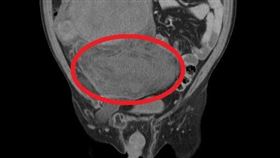

腹股溝腫脹30公分 竟惡性脂肪肉瘤

68歲的劉先生近日因腹部疼痛就醫,經電腦斷層檢查發現...